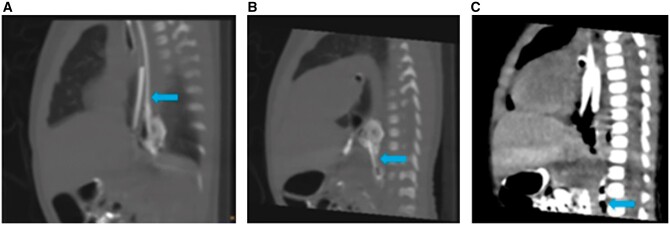

Intramural oesophageal dissection (IED) is an uncommon condition in newborns marked by the separation of the mucosal and submucosal layers of the oesophageal wall, both transversely and longitudinally, which may or may not involve perforation. A neonate presented at 26 h of life with poor respiratory effort and lethargy. She was intubated and was put on mechanical ventilation. Radiograph of the neonate suggested malpositioned endotracheal tube. The fluoroscopic dye-study indicated gastroesophageal oesophageal reflux disease and nothing significant. On limited CT contrast study of thorax, a tubular structure was seen running just parallel to the oesophagus extending from the T2 to the T9 levels. Possibilities of a oesophageal duplication/IED were considered. The neonate underwent an endoscopy and gastrostomy on day of life (DOL) 9. On follow up at 3 months a repeat limited CT study was done with instillation of water-soluble contrast. The previously seen tubular structure running parallel to the oesophagus was no longer seen. This finding suggested a healed IED. This case report emphasizes the significance of multimodality imaging in the diagnosis of this condition.